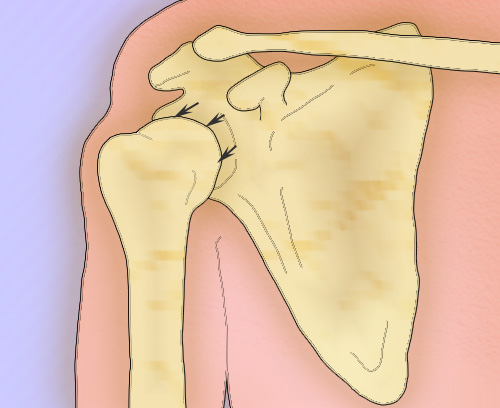

Вывих плеча со смещением головки плечевой кости вперед и вниз приводит к изменению контуров плечевого сустава, которые определяются визуально (см рисунок 1). Смещение плечевой кости при вывихе назад также легко диагностируется. Также при визуальном осмотре легко определяются передний вывих грудино-ключичного сустава и перелом ключицы. Во время осмотра врач должен обращать внимание на гипотрофию мышц лопатки и дельтовидной мышцы.

Рисунок 1. Передний вывих плечевой кости